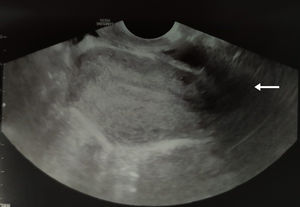

Caso clínicoSe expone el caso de una mujer de 17 años que presentaba estenosis del introito vaginal. Entre los antecedentes personales destacaba ser nuligesta, con menarquia a los 12 años y un patrón menstrual regular asociado a una intensa dismenorrea. No había iniciado relaciones sexuales por impedimento del canal vaginal ni tampoco podía ser usuaria de tampones. A la exploración, dificultada por dolor, se objetivaba un canal vaginal de apenas 3cm de profundidad sin lograr palpar el cérvix uterino; el resto de la exploración fue normal. A la ecografía transrectal no presentaba anomalías en el aparato reproductor. Ante estos hallazgos se solicitó una resonancia magnética nuclear (RMN) pélvica en la que no se evidenciaron alteraciones morfológicas en los genitales internos ni externos. Con estos resultados se decidió realizar una exploración bajo anestesia. En dicha intervención se apreció un TVT en la unión del tercio medio e inferior vaginal (fig. 1). En la ecografía transvaginal intraoperatoria se observó una sombra sónica correspondiente con el tabique (fig. 2). En la presión digital en dirección rectal bajo control ecográfico se produjo la apertura del canal (fig. 3) y se halló una vagina y cérvix morfológicamente normales. En la revisión a los 2 meses, durante los cuales la paciente usó dilatadores vaginales, presentó mejoría de la sintomatología y una exploración genital normal.

Pruebas como la RMN, actual gold stantard, ecografía y la tomografía axial computarizada tienen algunas limitaciones en el diagnóstico y diferenciación de malformaciones genitales3,12; de hecho, en la RMN realizada a nuestra paciente no se detectó el TVT como tampoco se pudo diagnosticar en el caso presentado por Ono et al.3. Esto puede deberse a la falta de acumulación de secreciones por ser perforado o al hecho de ser alto o delgado (2-3mm)6. Se han descrito otras pruebas, como la sonocolpografía de infusión salina, una técnica fácil y barata realizada bajo control ecográfico que proporciona información como el grosor y ubicación del tabique y la presencia o no de cérvix uterino3,12. El diagnóstico de perforación o no del TVT es esencial para prevenir secuelas como endometriosis, abscesos tuboováricos o piohematocolpos6.